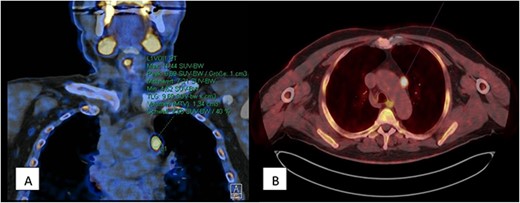

A 70-year-old man with a body mass index (BMI) of 32.6 presented himself 2021 with a history of primary hyperparathyroidism and a subtotal resection of a goiter in 2003. In January 2021, his PTH level was 129 pg/ml and calcium level was 2.78 mmol/l. An external parathyroid scintigraphy in April 2021 did not conclusively detect a parathyroid adenoma. For further diagnostics a 567 MBq C-11-Methionin was carried out in July 2021. Here in the upper mediastinum, to the left of the aortic arch, an oval lesion showed increased amino acid metabolism, raising suspicion of an ectopically located parathyroid adenoma (Fig. 1). Due to difficulty access caused by mediastinal localization we indicated the robotic- assisted approach in order to perform the parathyroidectomy.

567 MBq C-11-Methionin (A) coronary view of upper mediastinum, (B) axial view with oval lesion with increased amino acid metabolism left of the aortic arch.